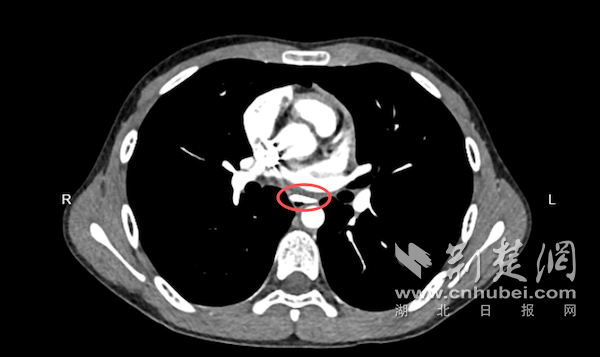

抵院后,医护人员为小轩完善了胸部增强CT检查,结果显示:异物位于胸段食管腔内,大小约26mm×16mm×5mm,形状为三角形,像一块小“匕首片”卡在食管中,距离主动脉仅约1.1mm,随时可能刺破血管,引发生命危险。

小轩胸部增强CT检查结果。通讯员供图